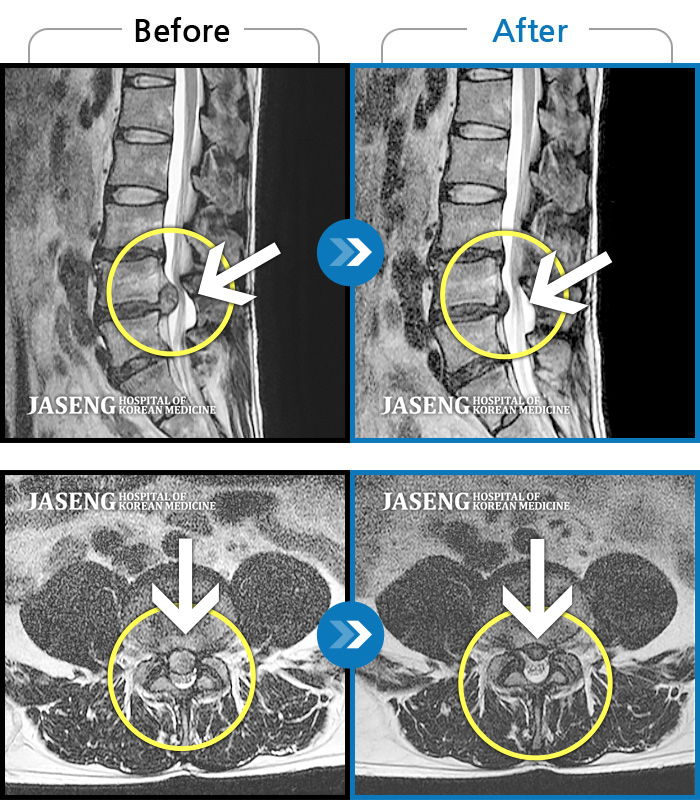

• 허리디스크